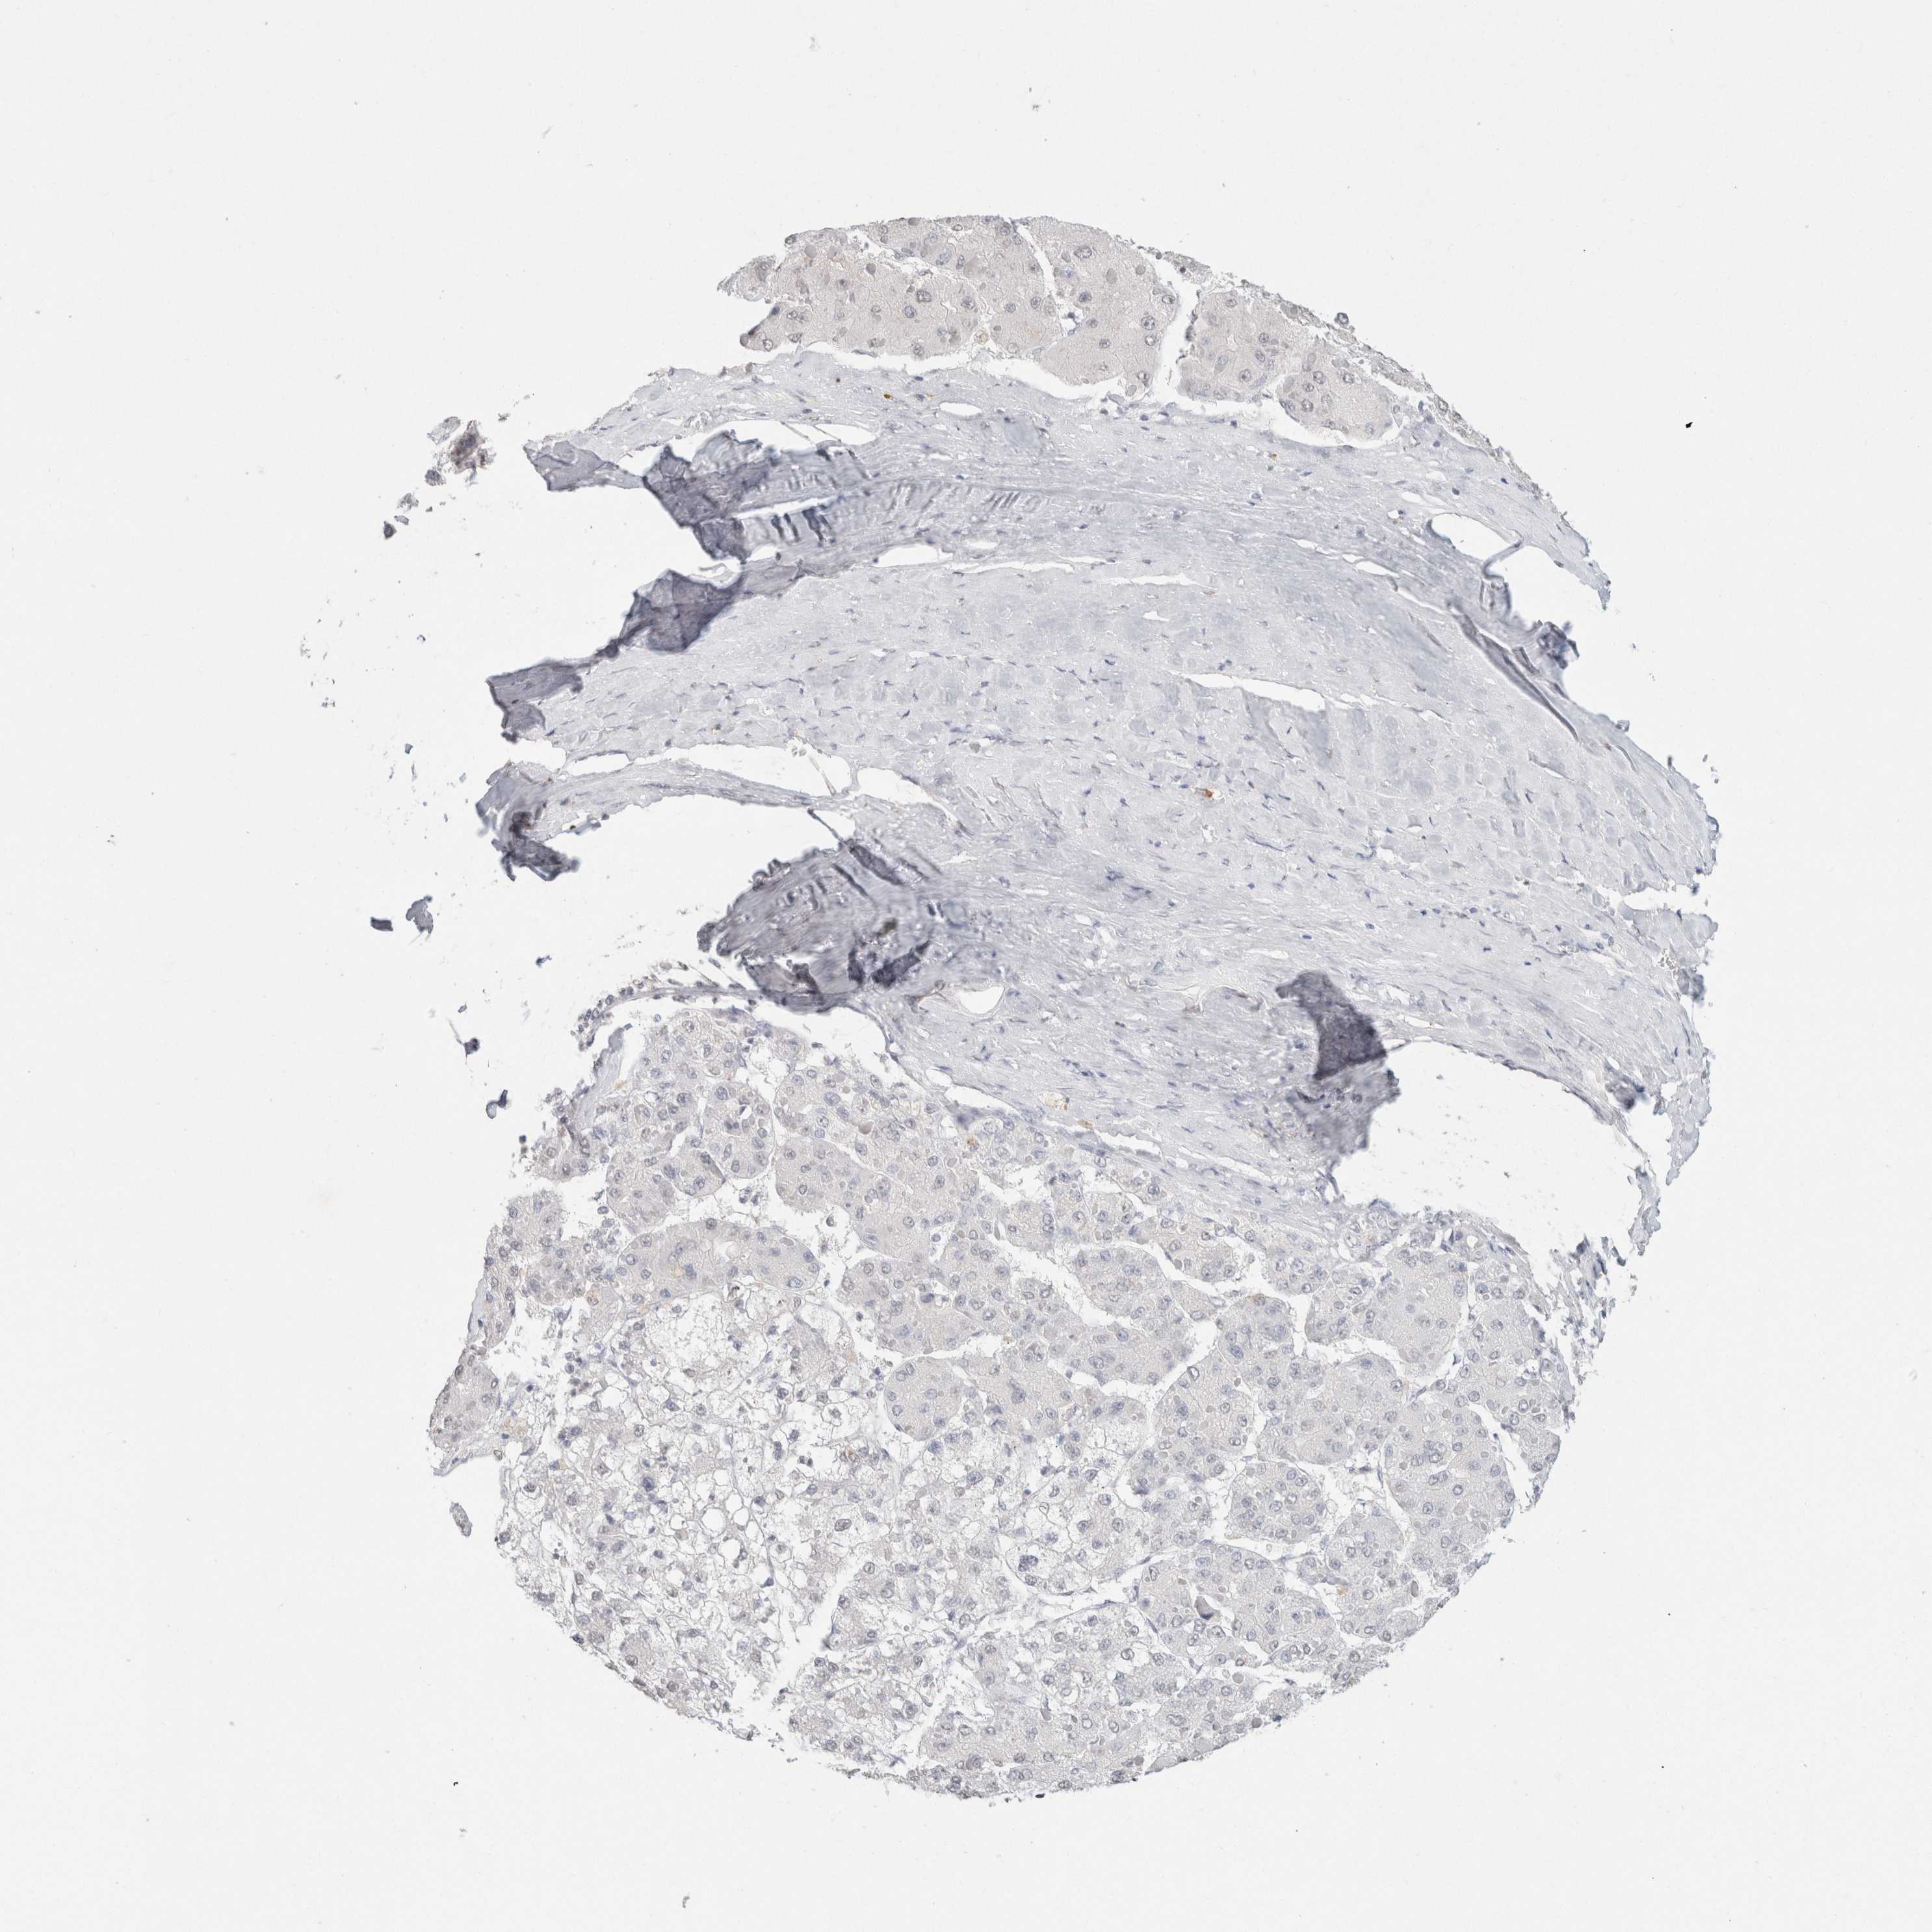

LIVER CANCER - Protein expressioni

A mouse-over function shows sample information and annotation data. Click on an image to view it in a full screen mode. Samples can be filtered based on level of antibody staining by selecting one or several of the following categories: high, medium, low and not detected. The assay and annotation is described here.

Note that samples used for immunohistochemistry by the Human Protein Atlas do not correspond to samples in the TCGA dataset.

Antibody stainingi

Antibody staining in the annotated cell types in the current human tissue is reported as not detected, low, medium, or high, based on conventional immunohistochemistry profiling in selected tissues. This score is based on the combination of the staining intensity and fraction of stained cells.

Each image is clickable and will lead to virtual microscopy that enables deeper exploration of all samples and also displays staining intensity scores, fraction scores and subcellular localization as well as patient and tissue information for each sample.

Antibody HPA050092

Antibody CAB025368

Staining

High

Medium

Low

Not detected

Intensity

Strong

Moderate

Weak

Negative

Quantity

>75%

75%-25%

<25%

None

Location

Nuclear

Cytoplasmic/membranous

Cytoplasmic/membranous,nuclear

Carcinoma, Hepatocellular, NOS

Cholangiocarcinoma